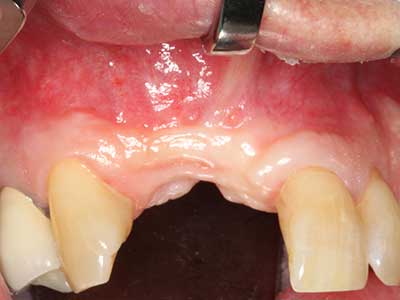

Il tessuto osseo non è semplicemente una struttura minerale, ma contiene anche una percentuale significativa di fibre di collagene. Ciò significa che non possiede solo una buona forza di compressione, ma anche un certo livello di flessibilità che è possibile sfruttare durante l'esecuzione degli accrescimenti di osso. Nella procedura di espansione classica con incisione ossea, la cresta alveolare atrofizzata viene incisa longitudinalmente ed espansa con cautela dopo aver raggiunto una profondità di osteotomia adeguata (figg. 13-16), idealmente senza una sostanziale rimozione del periostio (Brugnami, Caiazzo et al. 2014, Stricker, Fleiner et al. 2014). I sistemi a piastra e vite con distanza di espansione incrementale si sono dimostrati efficaci nella separazione delle due lamelle ossee restando al di sotto della soglia di frattura. In generale, sono richieste larghezze dell'osso residuo di almeno 3-4 mm (Chiapasco, Zaniboni et al. 2006) per garantire un'adeguata flessibilità e una copertura sufficiente dell'osso per gli impianti futuri. Se necessario, un'osteotomia di rilascio verticale su uno o più lati può migliorare la flessibilità. Una combinazione con ulteriori tecniche di accrescimento, in particolare dal lato buccale, è stata descritta come un'alternativa alla tecnica classica.